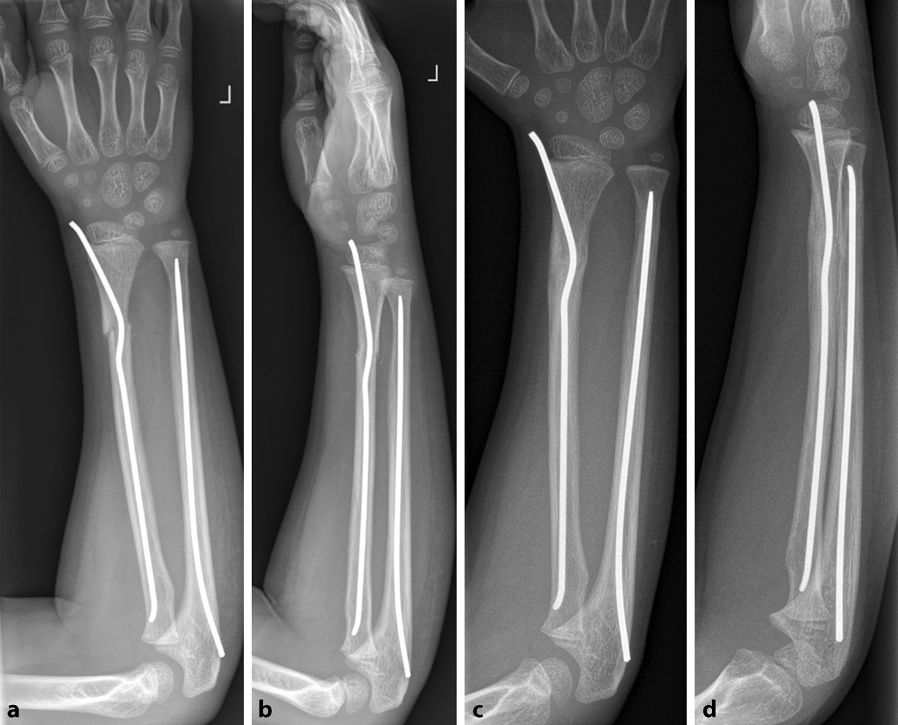

为解决上述问题,本文提出一种改良的弹性稳定髓内钉技术,用于治疗桡骨远端干骺端-骨干连接部骨折。

1. 经桡骨入点置入经皮髓内钉,直至抵达桡骨近端。

2. 将髓内钉回撤4cm。

3. :在入点近端4cm处将髓内钉弯折90°。

4. 将弯折段再次推送,直至抵达桡骨近端。